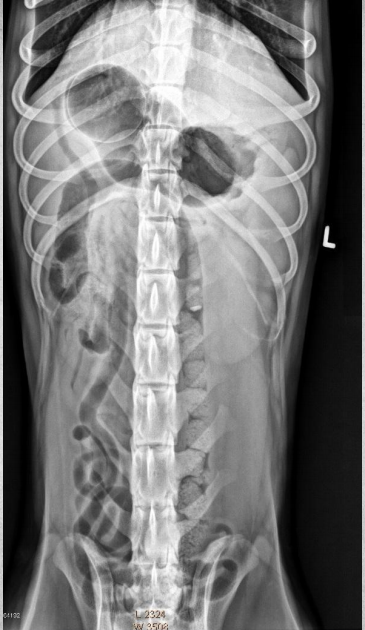

15 yo cat

Weight loss, anorexia, vomiting

Findings:

● Dilated bowel filled with fecal mass

– Not only large intestine, but small

intestine as well.

● Megacolon